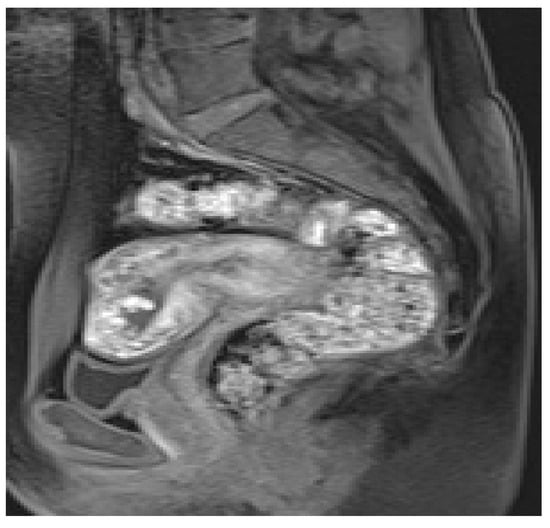

Masselli et al. showed that MRI could be a useful tool for identifying PA, with high soft-tissue contrast, wide field of view, and excellent interobserver agreement [49]. The authors observed that the diffusion and T1-weighted images have higher sensitivity and diagnostic accuracy (sensitivity, 100% and 94%, respectively; diagnostic accuracy, 100% and 97%, respectively) than the T2-weighted half-Fourier RARE (sensitivity, 94%; diagnostic accuracy, 87%) and true FISP sequences (sensitivity, 79%; diagnostic accuracy 90%) in detecting hematomas. Moreover, according to changes in signal intensity of hemoglobin in placental tissue on T1 and T2WI, MRI is able to estimate the age of bleeding (Figure 3) [49].

Hyperacute hemorrhage is typically hyperintense on T2-weighted and DW images, being intermediate on T1-weighted images. Acute hemorrhage shows a drop of signal intensity on T2WI, resulting in a hyperintense T1WI. Subacute hemorrhage is hyperintense on T1WI due to the paramagnetic effect of methemoglobin. Chronic bleeding is hypointense on T1WI and T2WI. The finding of a hyperacute or acute placental hematoma should warn of the risk of progression to a higher degree of abruption, whereas subacute or late bleeding is usually stable [13,49,51]. Therefore, an accurate and timely diagnosis of PA and the prediction of its worsening are crucial when considering conservative treatment. A potentially unstable patient requires continuous monitoring and emergency preparedness. Since the diagnosis of PA is based on clinical features and not on imaging findings, MRI is not routinely performed; however, this method is extremely accurate for placental assessment, identifying the cause of second- and third-trimester uterine bleeding. MRI should therefore be considered after negative US, especially if the diagnosis of abruption could change management [13,54].